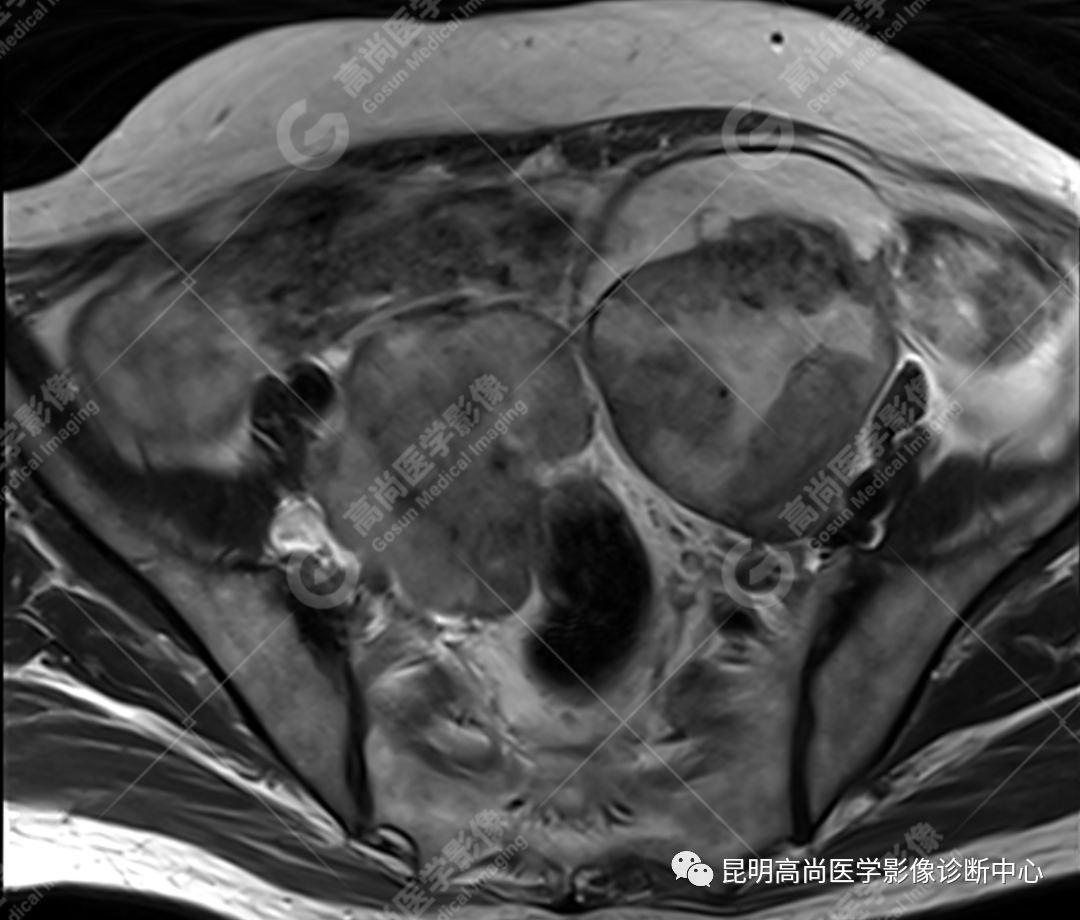

检查图像

影像诊断

子宫、附件未见显示;下腹部及盆腔内巨大占位,考虑恶性肿瘤,肉瘤可能,阴道及肛管受侵,建议活检。

MRI 表现

不规则菜花状或息肉状肿物,子宫内膜正常 T2WI 清晰连续的高信号消失,取而代之是中高、高信号,不均匀混杂信号,信号强度低于内膜正常信号强度,T1WI 上内膜信号增高,子宫肌层明显变薄,未受侵者肌层信号均匀,因肿物组织来源不同,病变信号复杂,以 T2WI 表现为等高混杂信号为主。因病灶较大,可合并囊变坏死及肿瘤出血。

肌层到肿块内的血管流空信号,可提示肿瘤内有血供丰富的肉瘤成分,血管流空信号在子宫内膜癌中未见报道,但在子宫平滑肌瘤、平滑肌肉瘤中可见。